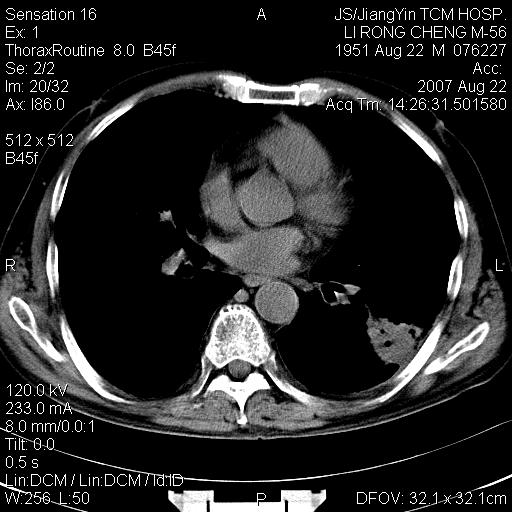

左肺下叶支气管呈小囊状扩张。下叶背段有类圆形高密度影,边缘模糊,外与胸膜相连。左侧胸膜增厚粘连。心包膜增厚。结合病史考虑1支扩并感染2胸膜及心包炎。

左下肺团片状类软组织密度影,形态不规则,边缘欠规整,其内可见液化区及气体影,病灶内侧见引流支气管影,相邻胸膜反应性增厚。病灶周围肺野内见增粗支气管,壁厚,边缘模糊。考虑:支气管扩张并感染;肺脓肿。

1:病灶不是实质肿块形态,胸膜脂肪间隙存在!

2:周围有卫星病灶,不象阻塞性肺炎

3:往下间质增厚,播散征象.